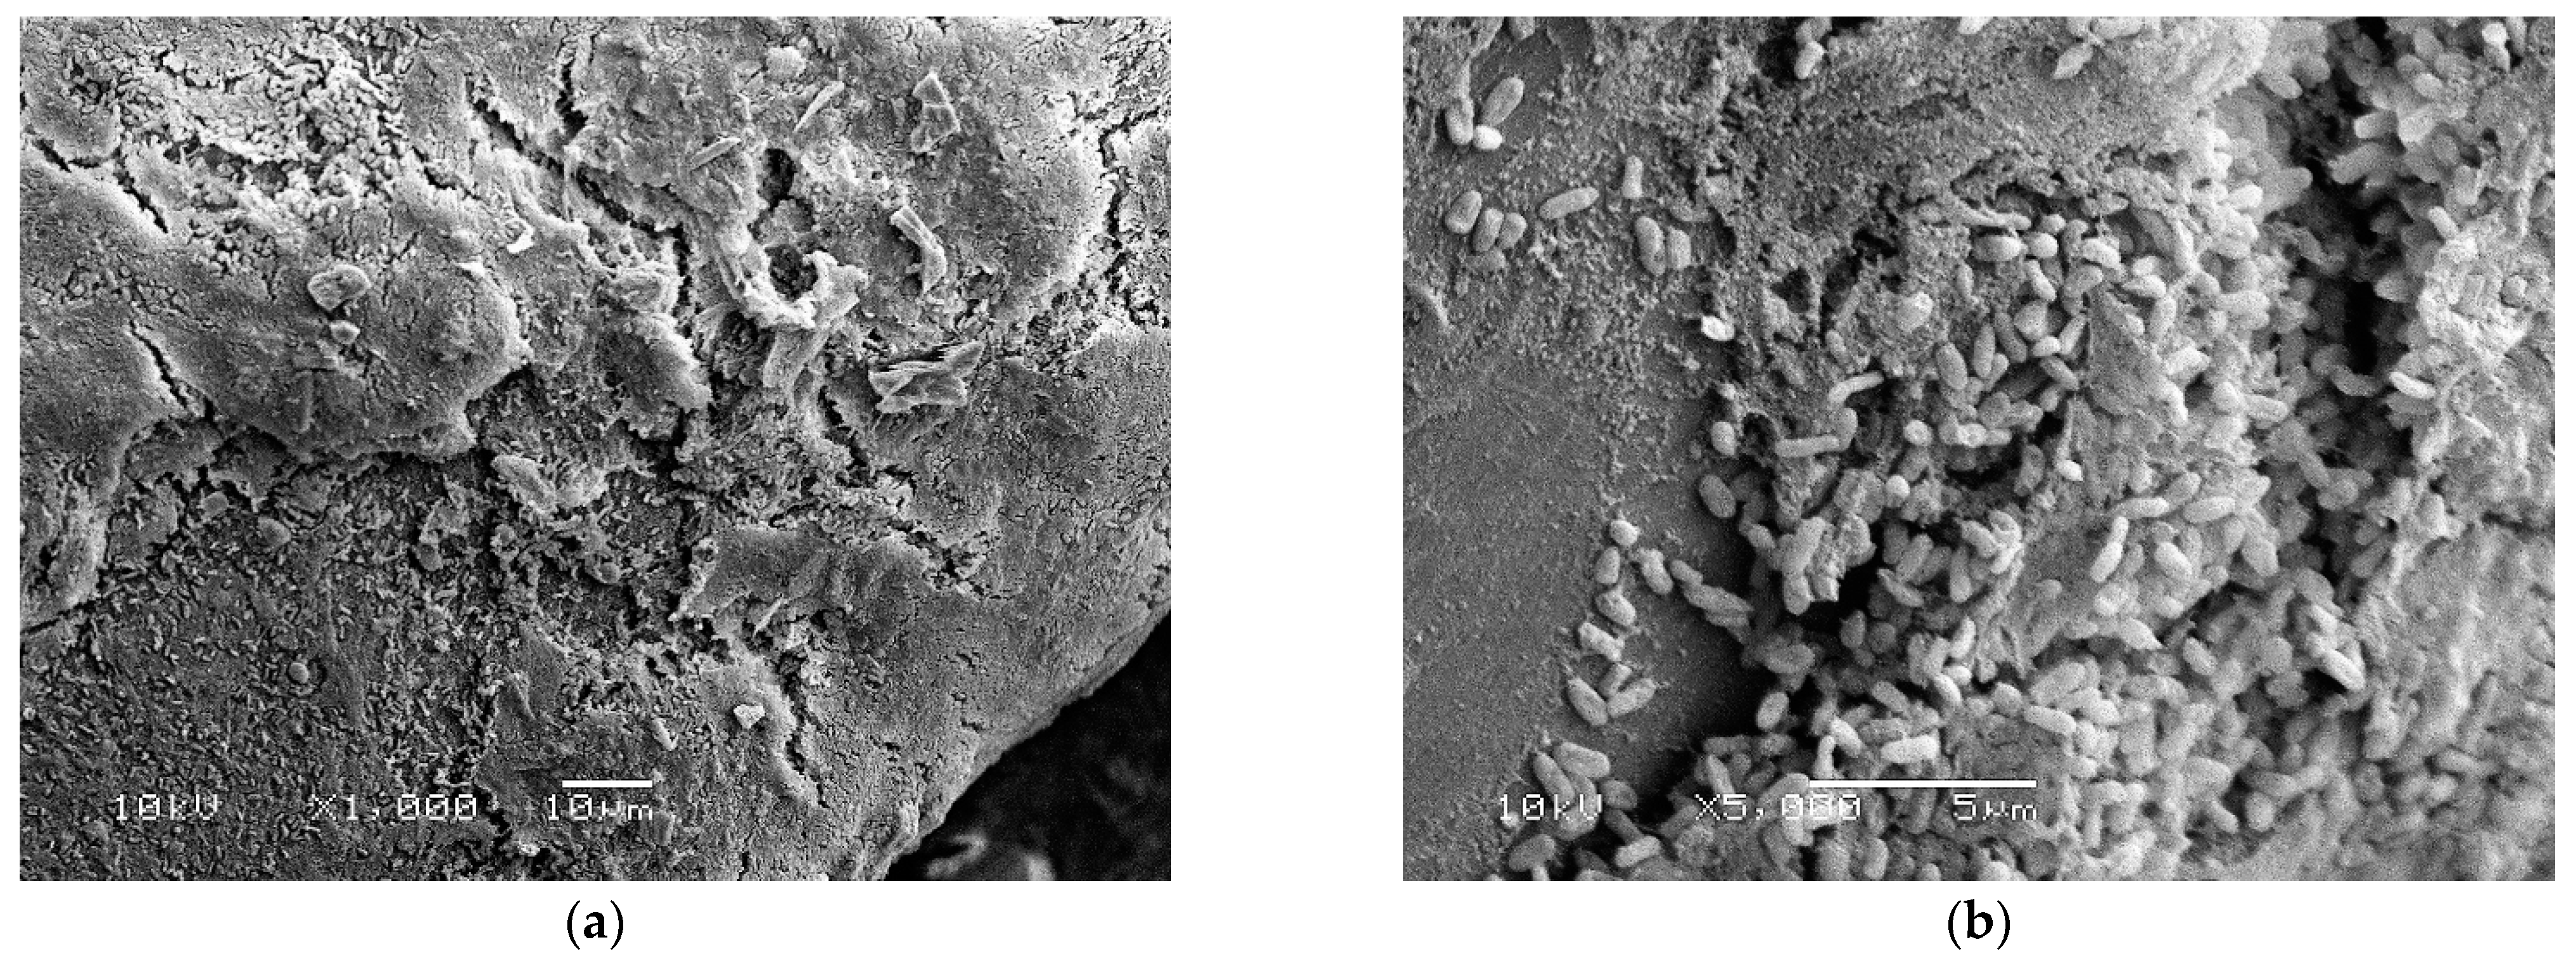

3.4. Scanning Electron Microscopy